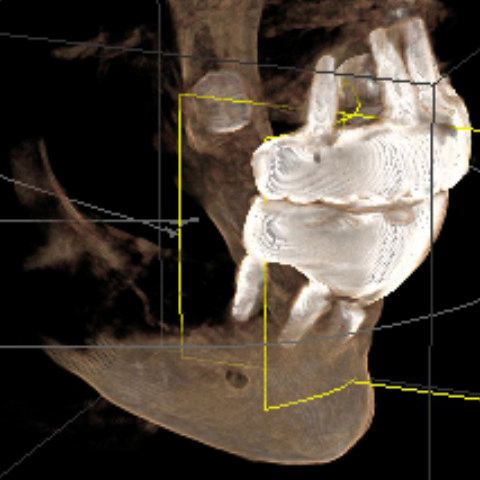

There are several issues with all of the implants, from problems with their locations, problems with mismatched heights from one implant to another, problems with their depth requiring gum grafts as there is no attached gingiva, problems with two of the upper implants apparently touching each other per periodontist report, a few other issues, and all seem to have some level of bone loss around the implants.

All the problems with the implants are creating all sorts of uneven pressures on the implants and my jaws. Implants were carelessly placed haphazardly, then Bansal bragged about how he had never completed a full mouth surgery in such a short amount of time as it took to do my mouth.

Among other things, the surgical experts told me that the success of such a laser treatment on that implant was very questionable. In addition, because of all the other problems with all of the lower implants, the best plan would be to remove that implant along with the rest of the lower implants. I'll be detailing some of the lower implant problems today. Some of the experts outright said that implant was failed and should just be removed. It's only a matter of time until that implant falls out on its own or when the screws are removed for a prosthesis cleaning.

There is also an unused implant buried in the center of my lower jaw which has severe bone loss which all the experts said must be removed. That implant poses a significant threat to my health. The bone loss pocket surrounding that implant is a magnet for pathogenic anaerobic bacteria that can have a devastating effect on my jawbone. This condition leads to progressive bone destruction, implant failure, and significant cosmetic changes.

According to the dental experts I consulted, the haphazard placement of the implants that Bansal did creates all sorts of uneven pressures on the implants, the prosthesis, and my jaws. That explains the problems with the temporary prosthesis breaking at the screws, as well as the screws loosening and unusual bone loss at the implants.